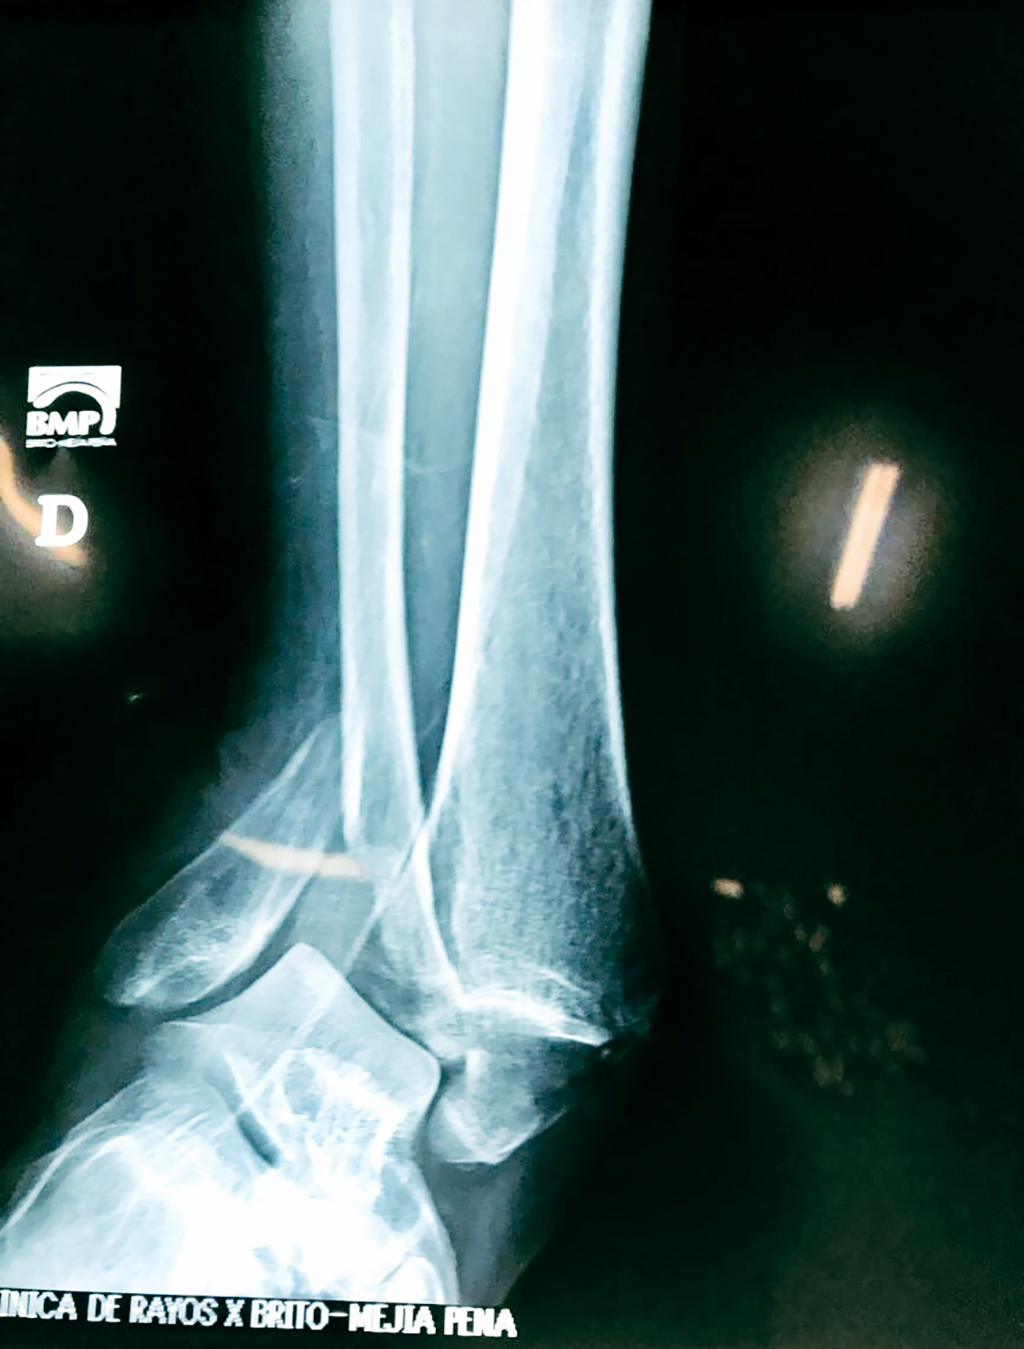

Una fractura de tobillo es la rotura de uno o más de los huesos del tobillo. Estas fracturas pueden ser:

- Parciales (el hueso está sólo parcialmente fisurado, no del todo).

- Completas (el hueso está perforado y está en 2 partes).

- Los extremos de los huesos están desalineados entre sí (desplazados).

- La fractura se extiende hasta la articulación del tobillo (fractura intra-articular).